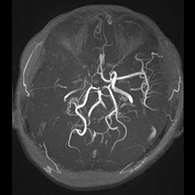

38歳、もやもや病、左半身一過性脳虚血発作

<画像所見>

(脳血管の脱落、赤丸部)

<術後画像検査>

術後はバイパス血管が脳内に向かって出現している(赤丸印)。